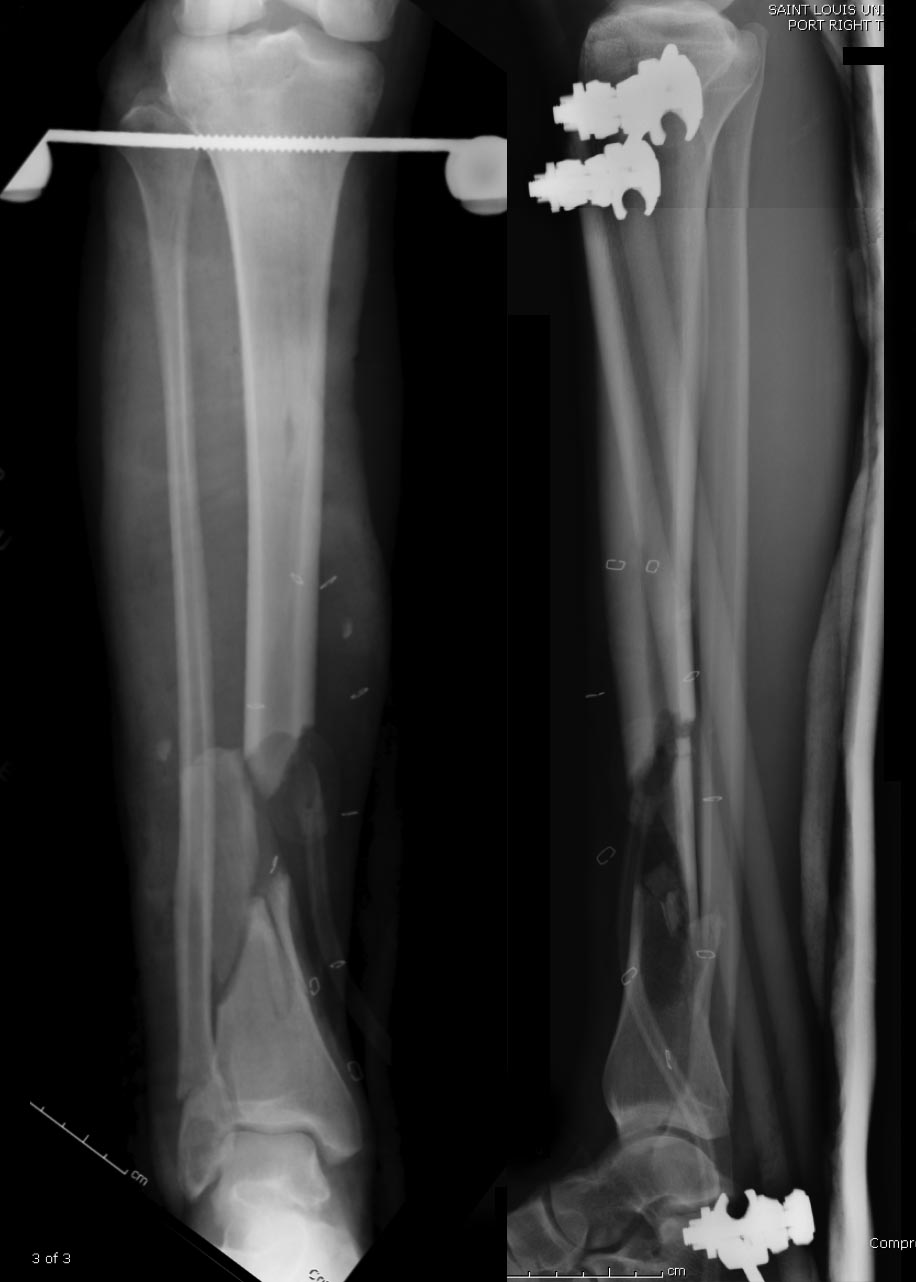

Данный случай не огнестрельная рана, а результат мотоциклетной аварии.

Независимо от повреждения при таких обширных дефектах мягких и костной

тканей применяется схожая тактика. Как видно, после нескольких I&D для

создания “pseudo membrane” применили цилиндрический блок из цемента.

Дефект мягких тканей закрыли свободным Anterior Thigh Graft. Из малого

доступа цилиндр удален небольшими кусочками, а пространство заполнили

бусами для освобождения пространства. По мере приближения регенерата

освободили пространство удалением бус через небольшой разрез. Этап

созревание регенерата можно было ускорить усилением интрамедуллярным

гвоздем, но решили закончить методом Илизарова.